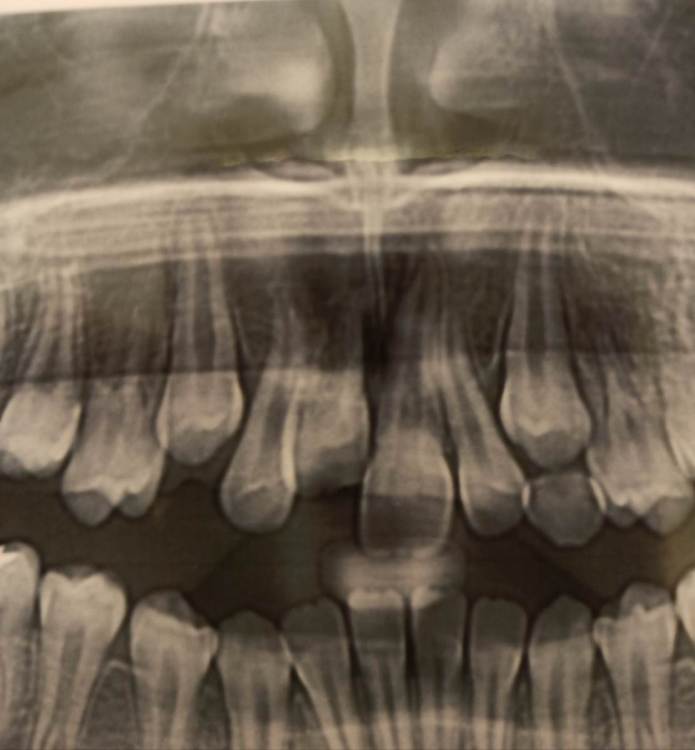

wladdX Опубликовано 4 июля, 2021 Поделиться Опубликовано 4 июля, 2021 Насколько могу судить по приложенным скринам, резорбция корня всё же есть. Судя по Вашему рассказу, проведённая коллегами работа была верной, результат весьма неплохой. Рассчитывать на длительное пребывание зуба 11 в челюсти не приходится. Когда-то его придётся удалить. 1 1 Ссылка на комментарий

Pole4ka Опубликовано 4 июля, 2021 Автор Поделиться Опубликовано 4 июля, 2021 38 минут назад, wladdX сказал: Насколько могу судить по приложенным скринам, резорбция корня всё же есть. Судя по Вашему рассказу, проведённая коллегами работа была верной, результат весьма неплохой. Рассчитывать на длительное пребывание зуба 11 в челюсти не приходится. Когда-то его придётся удалить. Спасибо большое за Ваше мнение и отклик! Нам бы дотянуть до момента, когда можно будет ставить имплант. Честно говоря, особой разницы между прошлогодним снимком (нижним среди снимков) и панорамным не вижу, поэтому возникла надежда, что резорбция приостановлена. А анкелоза нет? Спасибо! @wladdX Спасибо!!! Ссылка на комментарий

wladdX Опубликовано 5 июля, 2021 Поделиться Опубликовано 5 июля, 2021 Резорбция корня + вертикальное расположение = анкилоз. То что зуб был с несформированной верхушкой корня помогло ему простоять так долго после реплантации в растущей челюстной кости. Конечно, хорошо бы, чтоб зуб смог простоять до имплантации, но на мой взгляд это маловероятно. 1 1 Ссылка на комментарий

Pole4ka Опубликовано 6 июля, 2021 Автор Поделиться Опубликовано 6 июля, 2021 @wladdX @wladdX @wladdX 04.07.2021 в 21:44, wladdX сказал: 04.07.2021 в 22:25, Pole4ka сказал: @wladdX 20 часов назад, wladdX сказал: Резорбция корня + вертикальное расположение = анкилоз. То что зуб был с несформированной верхушкой корня помогло ему простоять так долго после реплантации в растущей челюстной кости. Конечно, хорошо бы, чтоб зуб смог простоять до имплантации, но на мой взгляд это маловероятно. Очень жаль, что такой неутешительные прогноз. Нам бы конечно дотянуть до имплантации. Но ведь за год изменений между двумя снимками практически нет, даже внешне (на снимках) стало чуточку лучше. И зуб не изменил цвет и неподвижный. Или это вообще ни о чем не говорит? Спасибо! Вверху 2021 год - панорамный снимок, внизу 2020 - КТ Ссылка на комментарий

Bier Опубликовано 6 июля, 2021 Поделиться Опубликовано 6 июля, 2021 Я вас не порадую: 1. Зуб анкилозирован. 3 часа в физрастворе = нет шансов на реваскуляризацию пульпы и связки. Судя по вашим снимкам однозначно анкилозирование. 2. Что делать теперь и почему: Зуб начал отставать в росте, еще через несколько лет это превратится в нерешаемую эстетическую проблему (вся челюсть будет расти, а зуб и участок челюсти с зубом - нет). Необходимо провести операцию декоронации (спилить коронковую часть зуба глубже уровня костной ткани, удалить то, что осталось от пульпы и дать так зажить. Остатки корня резорбируются сами с замещением на кость. Зато челюсть будет расти вместе с отстальными зубами. восстановить зуб временно на пластике (съемной) потом на брекетах. Имплантация желательно не раньше 21 года. Оставлять так нельзя! Ссылка на комментарий